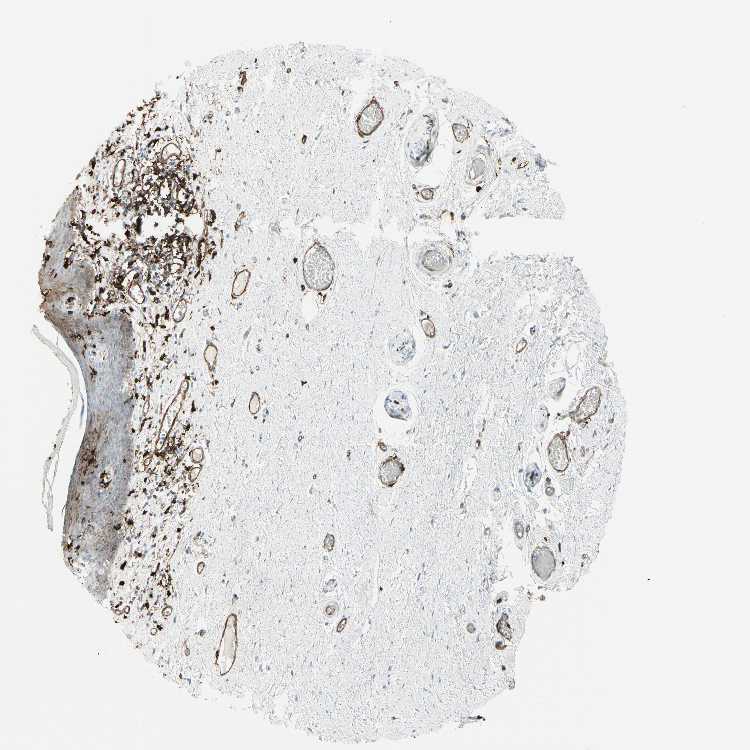

SKIN 2 - Antibody stainingi

Antibody staining in the annotated cell types in the current human tissue is reported as not detected, low, medium, or high, based on conventional immunohistochemistry profiling in selected tissues. This score is based on the combination of the staining intensity and fraction of stained cells.

Each image is clickable and will lead to virtual microscopy that enables deeper exploration of all samples and also displays staining intensity scores, fraction scores and subcellular localization as well as patient and tissue information for each sample.

Antibody HPA011078

Epidermal cells Medium